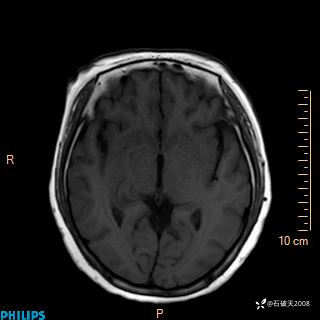

颅内占位,影像征象不是很丰富,有病理

hyy838 推荐女 62岁 主 诉:头晕12小时,加重1小时。

现病史:患者于12小时前无明显诱因出现头晕,呈持续性,无天旋地转及行走不稳,伴恶心、呕吐,呕吐共5次,呕吐物为胃内容物(具体性质不详),无胸闷、胸痛、心慌,无腹痛、腹泻,无咳嗽、咳痰,无发热、意识不清、肢体抽搐及大小便失禁等,1小时前患者上述症状加重,未诊疗,为求进一步治疗急自行来我院,门诊以“头晕待查”为诊断收入我科,发病来,神志清,精神差,饮食、睡眠差,大小便正常,体重未见明显下降。

T2